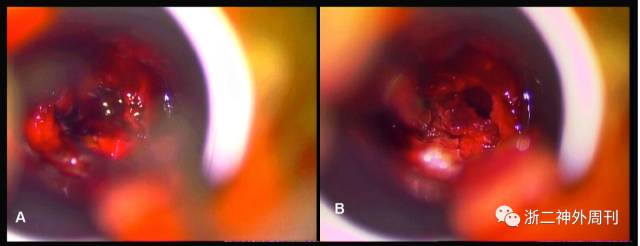

患者于2017.05.13突发头痛,伴呕吐一次,无视物模糊,无胸痛,无意识障碍。就诊于当地医院查心电图提示V1-V4 导联ST段抬高,肌钙蛋白0.021 ng/ml↑,血糖34.51mmol/l↑。当地医院诊断心肌梗塞后转诊我院心内科,查肌钙蛋白-T 0.038 ng/ml↑,糖化血红蛋白A1c16.4↑,β羟基丁酸0.75nmol/l↑,头颅CT提示鞍区少许高密度灶(图1A),我院心内科诊断:急性冠脉综合征、糖尿病酮症酸中毒 代谢性脑病。予双抗治疗,1天后由于患方拒绝任何检查治疗自动出院。

患者出院后回家,症状并无明显改善,2017.05.18日起出现头痛加重,神志淡漠,嗜睡,逐渐加重,2017.05.22再次就诊我院神经外科,查头颅CT提示蝶鞍扩大,鞍区高密度灶(图1B)。垂体磁共振增强提示鞍区占位伴出血。磁共振DWI相提示双侧额叶内侧及扣带回皮层下高信号,弥散受限,考虑急性脑梗塞(图2)。垂体激素提示:游离T3(FT3)1.74pmol/L↓、游离甲状腺素FT45.57pmol/L↓、总甲状腺素TT440.3nmol/L↓、皮质醇(8am)12.4nmol/L↓、黄体生成素<0.3IU/L↓、卵泡刺激素0.6IU/L↓。生长激素1.75ng/ml, IGF-1 79.3ng/ml↓,PRL79.3mIU/L正常。心电图提示前壁ST段抬高,肌钙蛋白-T 0.021ng/ml↑,空腹血糖14.0mmol/l↑,早餐后血糖16.2mmol/l↑。急诊拟“垂体腺瘤卒中,额叶梗塞,糖尿病”收住入院。

入院查体:生命体征正常,神志嗜睡,呼叫可睁眼,定向力差,不能正确对答,肢大面容,双手指粗大(图1C),视力检查不能配合,双侧瞳孔等大等圆约3mm,对光反射灵敏,四肢肌力V级,病理反射未引出。

图1. A. 5月13日头颅CT可见鞍区高密度影;B. 5月22日CT提示随着病情进展,垂体卒中显著加重;C. 患者显著肢端肥大面容,手指粗大。